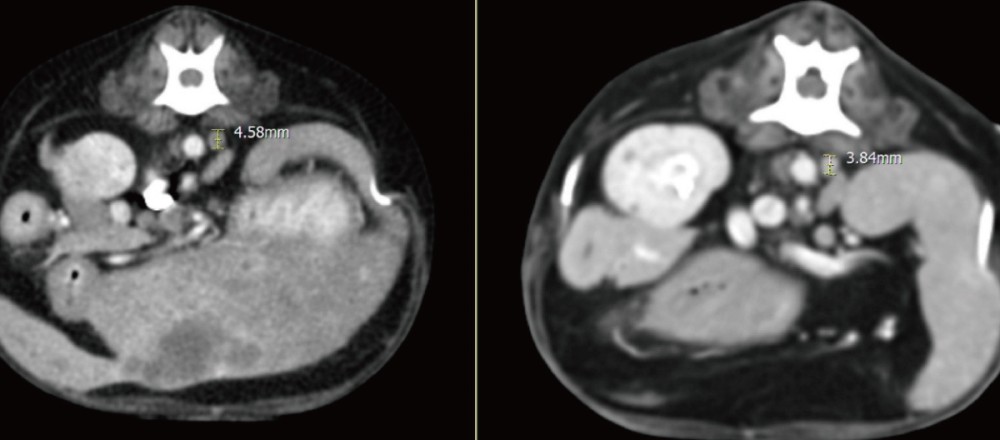

이러한 판단으로 초음파 유도 하에 pigtail catheter를 삽입하여 지속적인 배액을 시행하였습니다.

45dea41c691aea1975c51c7a51847d38_1775038397_276.png

이후 환자는 점진적인 임상적 호전을 보였습니다.

실제로 추적 CT에서도 간 내 낭성 병변의 크기가 뚜렷하게 감소하고 림프절 크기 또한 감소하여 처치에 대한 반응이 명확하게 확인되었습니다 .